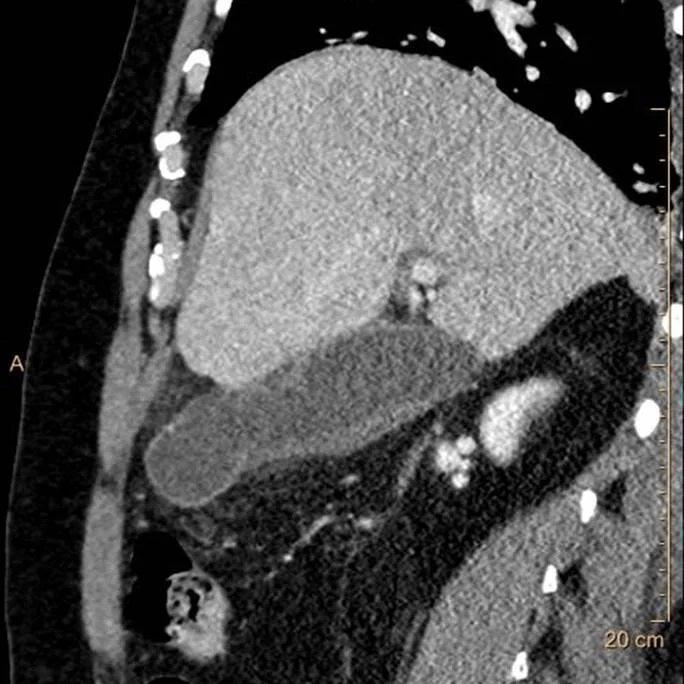

Iodine map also shows the same “hole”. Discontinuous enhancement is a very good sign of necrosis or perforation.